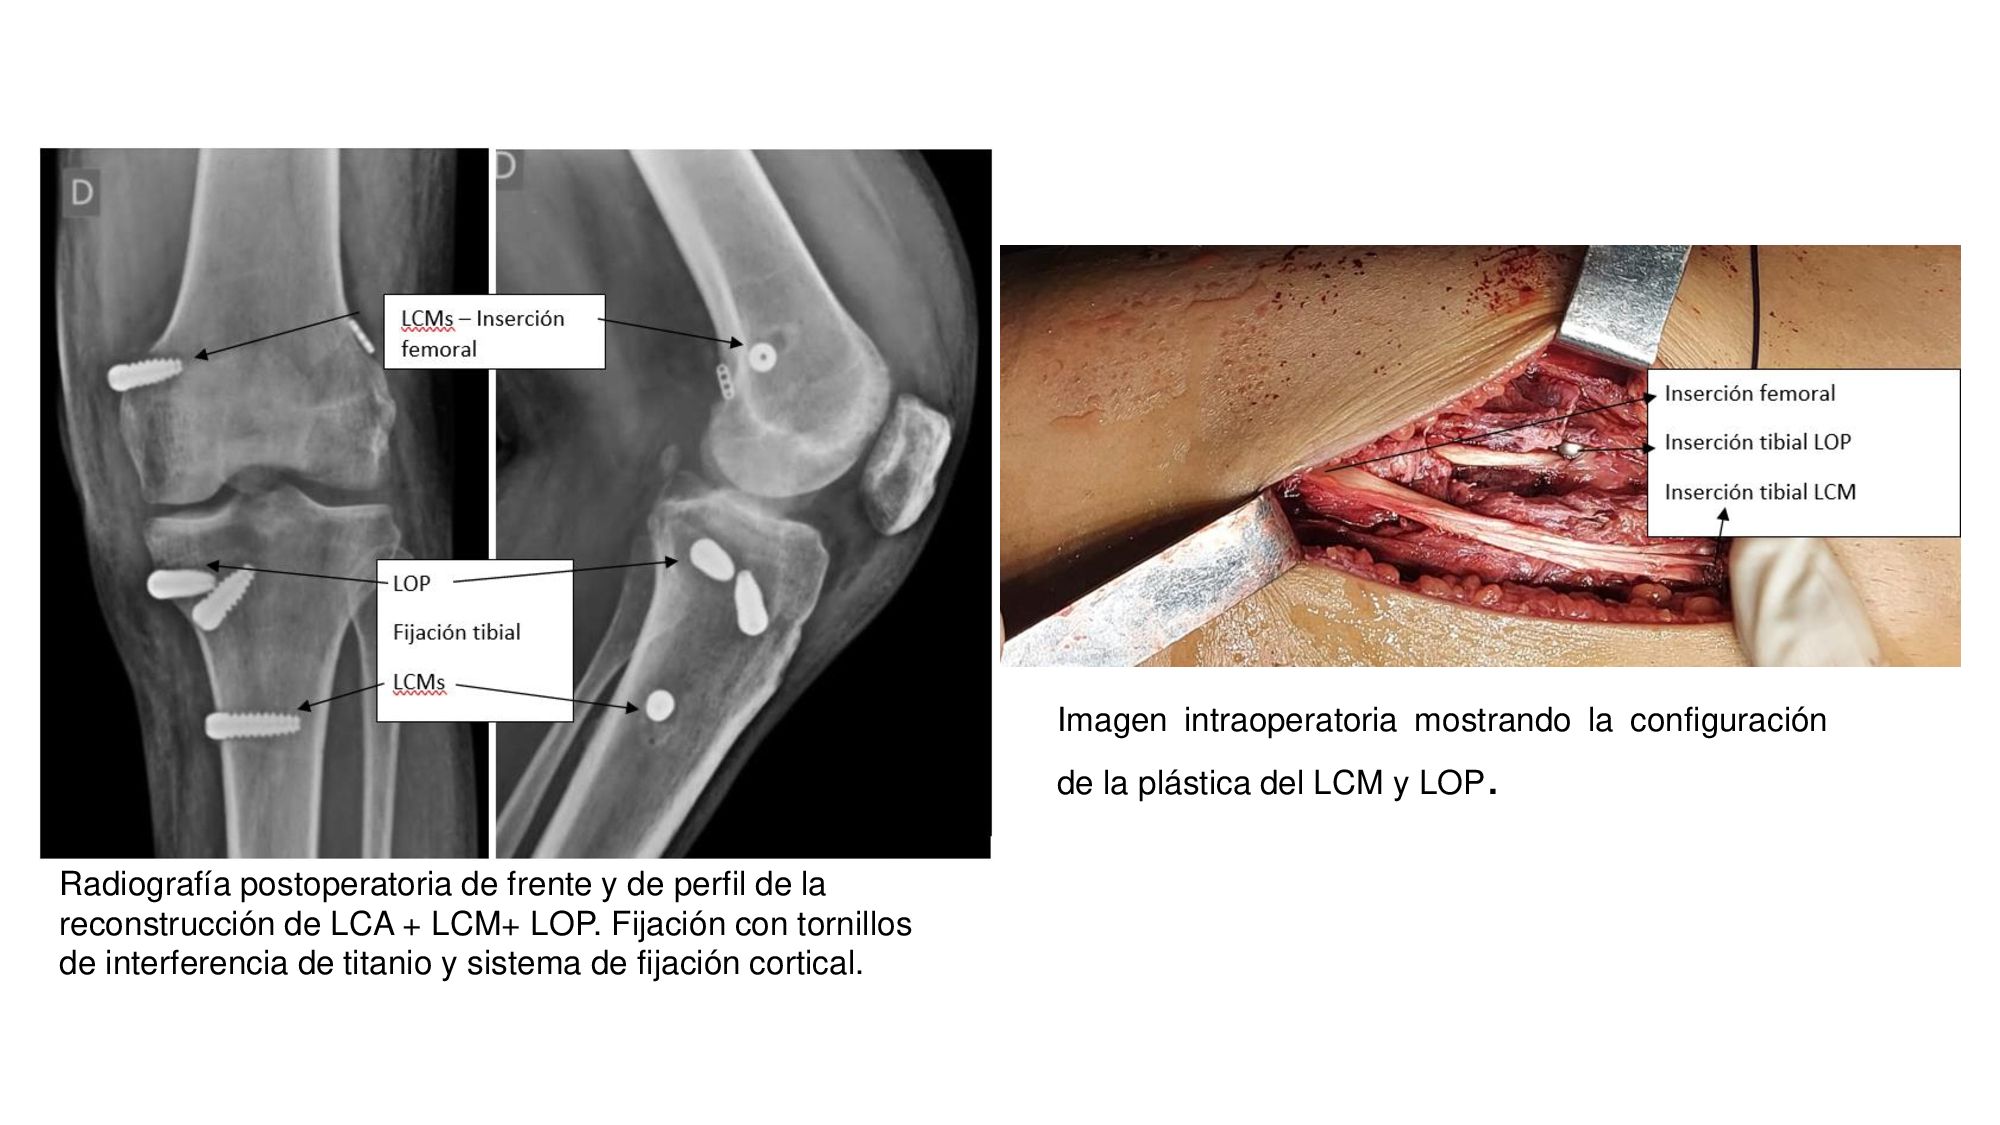

19_“Reconstrucción en fase aguda de ligamento colateral medial mediante técnica de túnel único femoral”

Dres. Carlos Daniel Nigito - Alan Manríquez - Diego González (Mendoza)